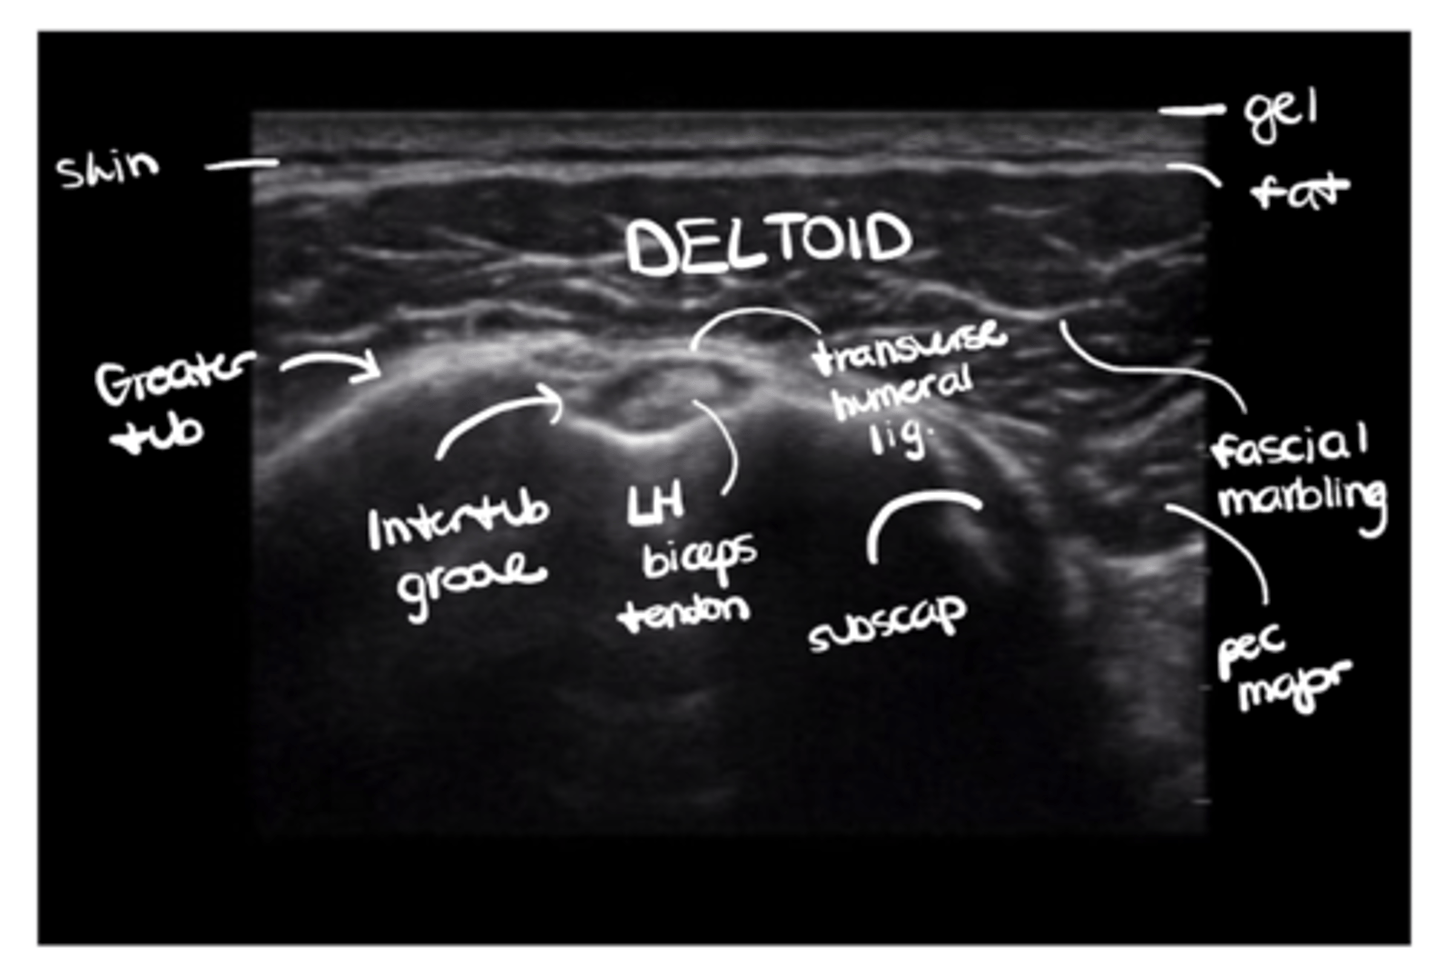

Run us through what you would see on an axial slice of the shoulder under ultrasound.

Gel --> skin --> fat --> deltoid w/ fascial marbling --> subscapularis + pec major in the mix --> greater tuberosity + transverse humeral ligament over the intertubercular groove --> LH biceps tendon

What would a transverse vs. longitudinal ultrasound of the shoulder look like?

See image.